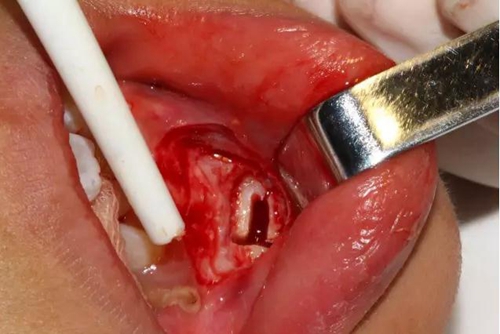

同時在剩余的根部斷面4MM下,預(yù)備2MM的溝槽,通過剝離子的三角尖端將牙體推出

三彎探針取出牙根部分